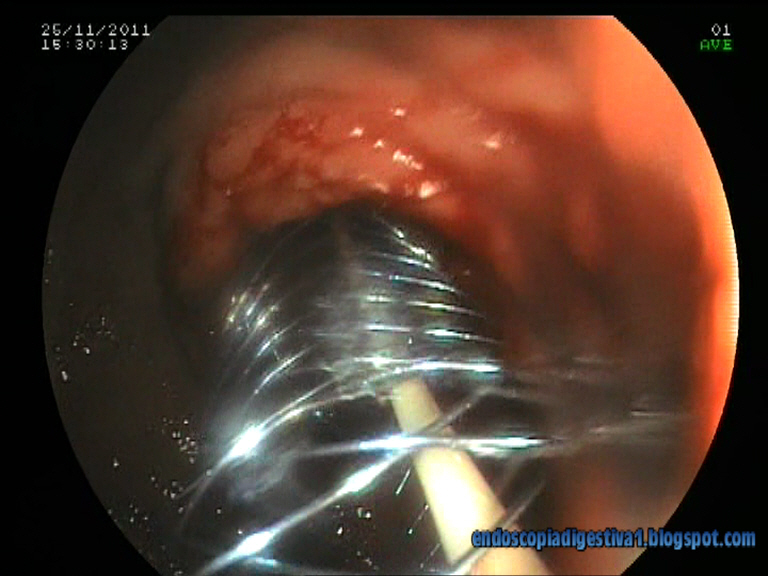

Paciente de 90 años de edad con antecedentes de cardiopatía isquémica, HTA, fibrilación auricular y DM tipo II que ingresa por anemia ferropénica severa (Hb 6.5 gr/dl), cuadro constitucional y vómitos en posos de café de un par de meses de evolución. Se realiza gastroscopia donde se aprecia una estenosis de aspecto neoplásico a nivel prepilórico, que no permite el paso del endoscopio. Las biopsias mostraron un adenocarcinoma gástrico ulcerado, poco diferenciado. El TAC realizado evidenció un engrosamiento de la pared gástrico a nivel antral y prepilórico con infiltarción de la grasa perigástrica y muy probablemente del mesocolon transverso, así como un nódulo de aspecto metástásico en la glándula suprarrenal izquierda (estadio IV). Se decide colocar una prótesis metálica no recubierta paliativa por vía endocópica para garantizar la nutrición de la paciente. Al no disponer en el momento de la colocación de una prótesis Wallflex duodenal, y tener solo Wallflex de colon de 12 cm, se decide usar esta última. Para ello se desenvaina la prótesis del sistema Placehit, se le da la vuelta para que la parte proximal de la prótesis sea la mas ancha y evitar la migración distal una vez colocada en la región antropilórica. La colocación cursa de forma exitosa aunque por su longitud, nos vemos obligados a dejar una mayor parte del stent en la cámara gástrica, pero de forma totalmente funcional.

Dentro de las obstrucciones malignas de la salida gástrica, este caso pertenece a las lesiones de la región antropilórica (mas proximales), generalmente secundarias a adenocarcinomas gástricos. Los otros dos tipos son las localizadas en el área piloro-duodenal y la postbulbar (2ª porción), mas relacionadas con la infiltración duodenal por cáncer de páncreas. En el caso que se expone, hay que intentar colocar la prótesis justo por encima de la papila para evitar la compresión de ésta y por ende la aparición de ictericia. La técnica usada por nosotros es la combinada endoscópico-fluoroscópica. En primer lugar se pasa una guía rígida de 0.035-0.038″ montada en un catéter de CPRE a través de la estenosis. Una vez que haya pasado la guía a las porciones mas distales del duodeno, se inyecta contraste y se mide la estenosis de forma aproximada. Posteriormente se coloca la prótesis sobre la guía. Es muy importante cuando se introduce la prótesis, para evitar perforaciones, traccionar ligeramente de la guía para evitar acodaduras del sistema. Finalmente se libera (sistema de liberación distal) la prótesis, sin prisas, ajustando los extremos (sobre todo distal en este caso). Para esta situación en particular, como se ha comentado anteriormente, al no disponer de Wallflex duodenal y si de colon, dado que son de características similares (en cuanto a material, diámetros proximales, distales, longitudes) y solo diferir en la posición de la parte de mayor calibre para evitar la migración (distal en colon y proximal en duodeno), se decidió desmontar la prótesis del sistema de liberación, darle la vuelta y con paciencia y algo de maña, montarla de nuevo.